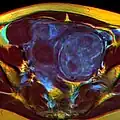

-

A very large (9 cm) fibroid of the uterus which is causing pelvic congestion syndrome as seen on CT -

MRI image with multiple uterine leiomyomas -